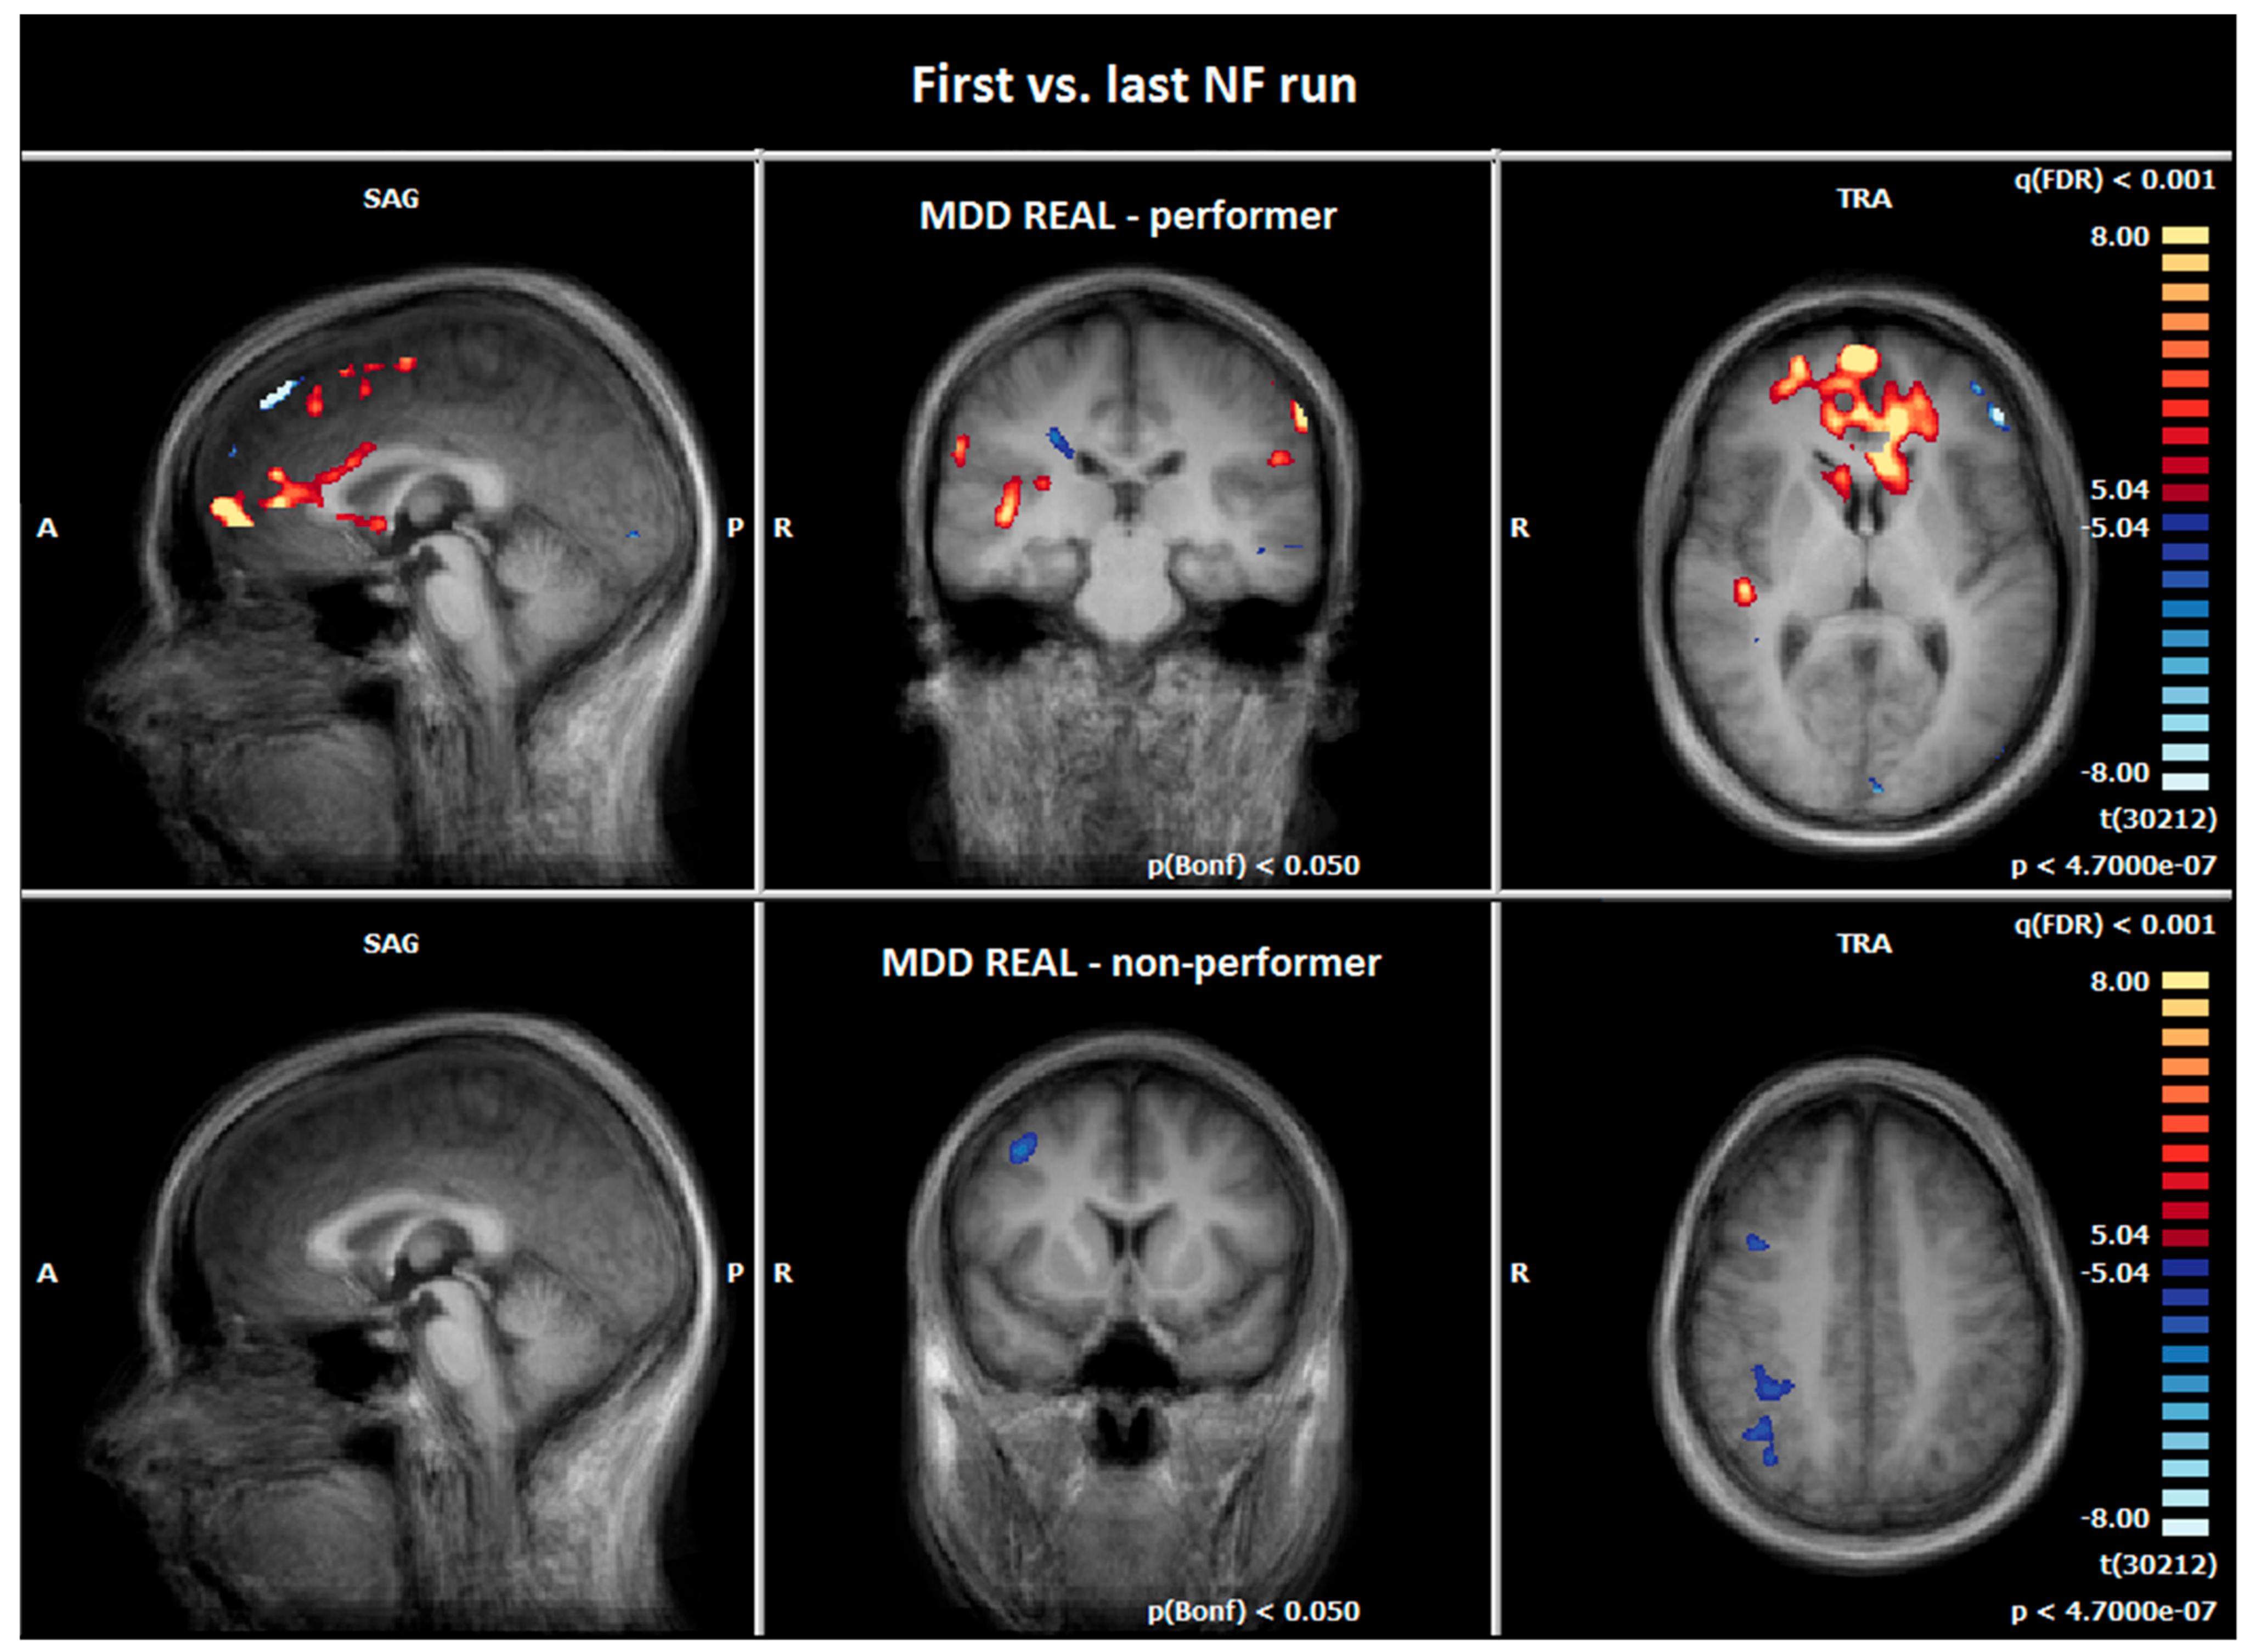

3.5. Comparison of Hemodynamic Responses between the First and the Last NF Run: MDD REAL Responder vs. MDD REAL Non-Responder

4.2.3. Comparison of Hemodynamic Responses between the MDD REAL Responder and MDD REAL Non-Responder: First vs. Last NF Run